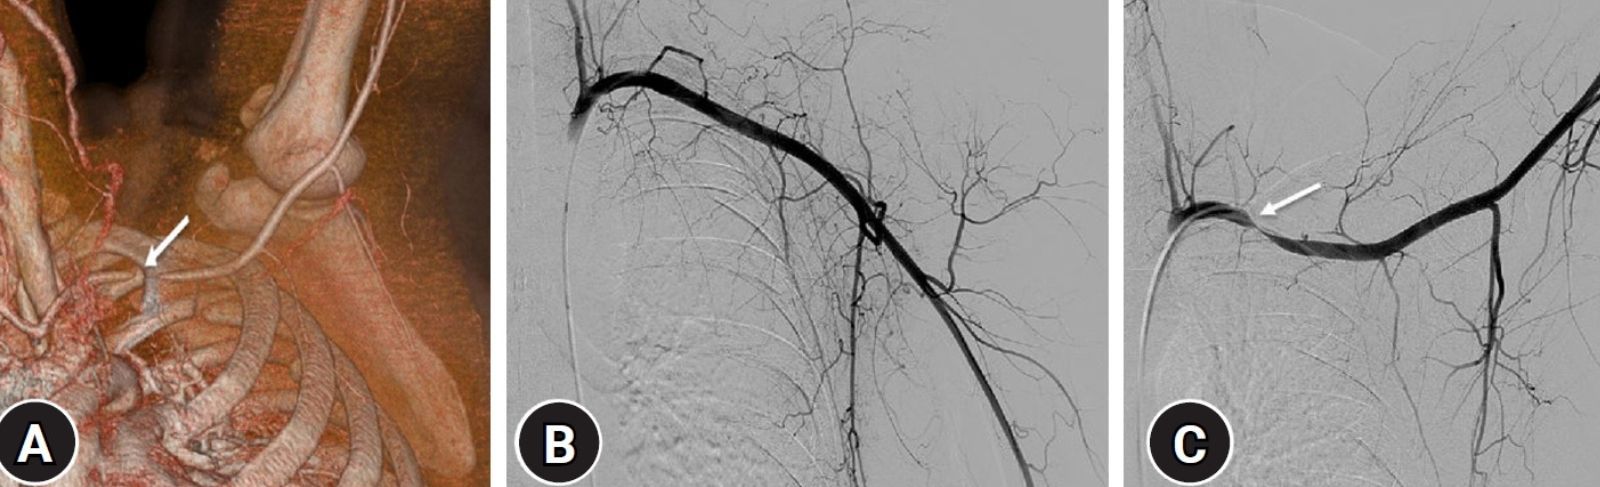

This revolutionary procedure represents a major breakthrough in the treatment of this diagnosis, which often affects younger active individuals, including athletes, and the most effective type of intervention is being sought for them. In upper thoracic aperture syndrome, there is compression of the neurovascular bundle in the region of the first rib. Patients suffer from pain, tingling, swelling, or immobility of the limb.

The young patient, who is a professional fencing athlete, underwent the surgery due to difficulties associated with blood vessel compression. The diagnosis of Thoracic Outlet Syndrome is most often confirmed in patients by MRI, CT or ultrasound in addition to clinical examination, and treatment begins conservatively with rehabilitation. Surgery is a last resort in cases where symptoms persist and limit the patient's normal life.